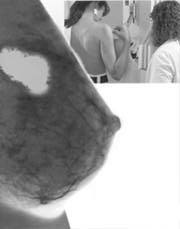

Los cánceres de seno, colon y próstata son los más malignos en occidente, relacionados con dietas altas en grasa; 30 por ciento de esos tumores están ligados con hábitos de comida.